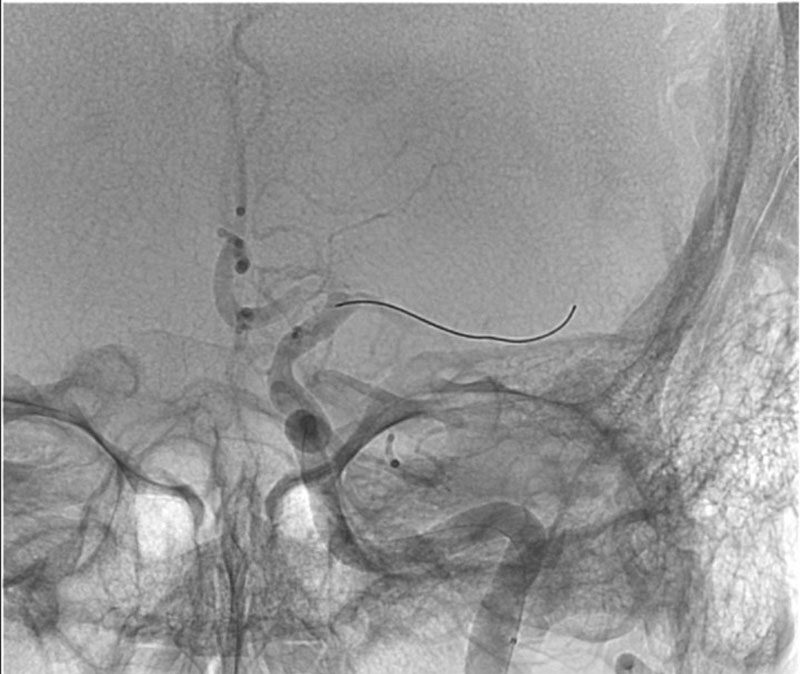

ICA-M1 intracranial dissection EVT

This clinical case presents a 28-year-old female patient presenting with a wake-up stroke, managed with endovascular treatment.

• 28 yo, Female

• Wake up stroke (LKW 02.00)

• NIHSS: 15

• No i.v. lysis

• CTA: 10.25

• Groin puncture: 11.07

EVT Strategy

• Inflate the balloon, in order to dilate the true lumen

• MCA access with the softest system possible

• Open a stentriever for 20 mins with antiplatelet infusion

• Resheath the stentriever, check patency, if not stent-deployment

Headway™ DUO 156cm / Traxcess™ 14

CatchViewMini20

pEGASUS 4x20mm